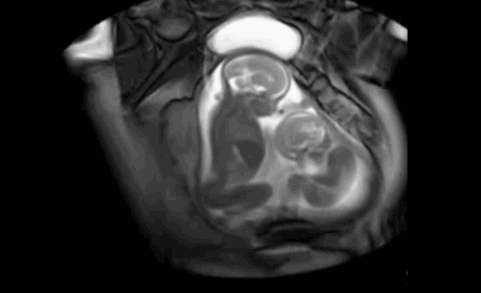

接着,小baby加猛攻势,大baby开始有所回应。